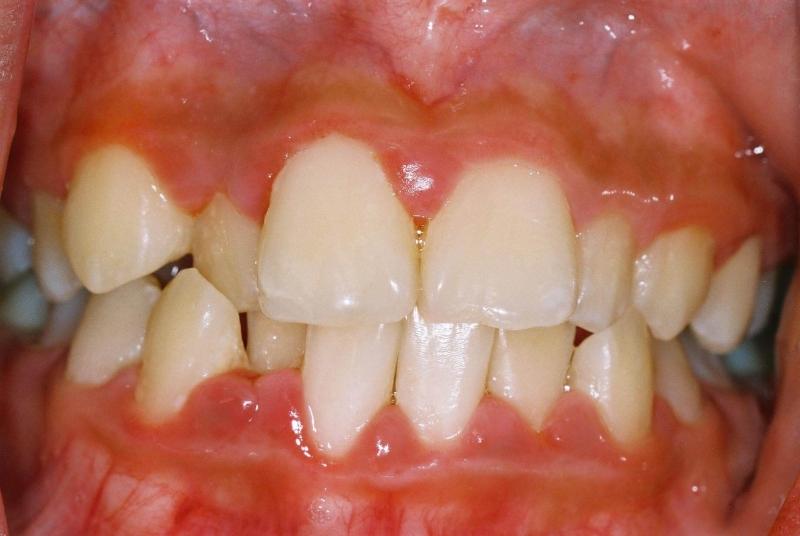

Острая форма катарального гингивита проявляется внезапно и отличается стремительным развитием, выраженной болью, ухудшением общего состояния и повышением температуры.

Ключевые симптомы включают:

- резкую боль в деснах;

- зуд и жжение в области воспаления;

- значительное покраснение слизистой оболочки в поражённой зоне;

- увеличение десневых сосочков;

- отёк и кровоточивость дёсен;

- общее недомогание, слабость, головные боли и повышение температуры.

Хронический катаральный гингивит (см. фото) представляет собой следующую стадию заболевания. Симптомы становятся менее выраженными и чаще всего проявляются в моменты снижения иммунитета, во время еды и чистки зубов.

Основные симптомы включают:

- болезненные ощущения при приёме пищи и гигиенических процедурах;

- кровотечение из дёсен во время чистки зубов;

- постоянная гиперемия поражённых десен;

- отслаивание межзубных сосочков от зубов;

- отёк краёв десен.

При осмотре полости рта врач обращает внимание на состояние десен, их цвет, текстуру и наличие отека. Для острого катарального гингивита характерно покраснение и отек десен, а также их болезненность при пальпации. Десны могут быть легко кровоточащими, особенно при чистке зубов или при легком нажатии. Важно отметить, что в отличие от других форм гингивита, при катаральном типе воспаление обычно ограничивается только деснами, без вовлечения более глубоких тканей.